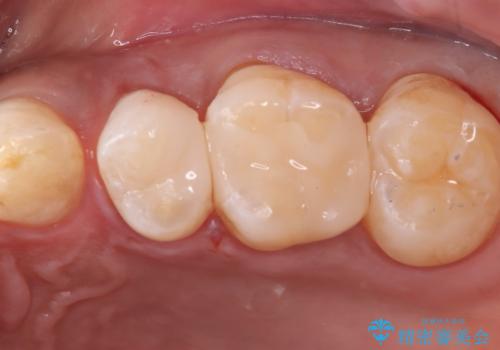

左上5番目の歯の側面に実質欠損を認め、隣の6番目の歯にも虫歯を認めたため両歯ともセラミックインレーでの治療となりました。

左上5番遠心に実質欠損を認め、さらに5番と6番の隣接面にもカリエスを認めました。6番の咬合面には、元々コンポジットレジン修復が施されており、劣化がみられたのでその部分も含め修復することとなりました。

セラミックインレーセット時は、ラバーダム防湿を行っています。